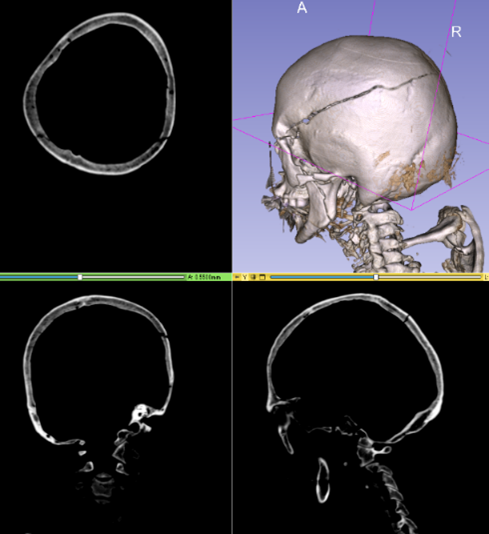

医用3D画像データ

頭蓋骨折を異常箇所として検出

2D画像では、例えば骨折を検出する際、亀裂の方向が画像面と平行に近くなるほど映りにくくなるため、連続性や分岐のような構造の把握が難しいという課題がありました。3D画像をそのまま学習させることにより、立体的な形状が把握できるようになりました。

異常箇所検出イメージ